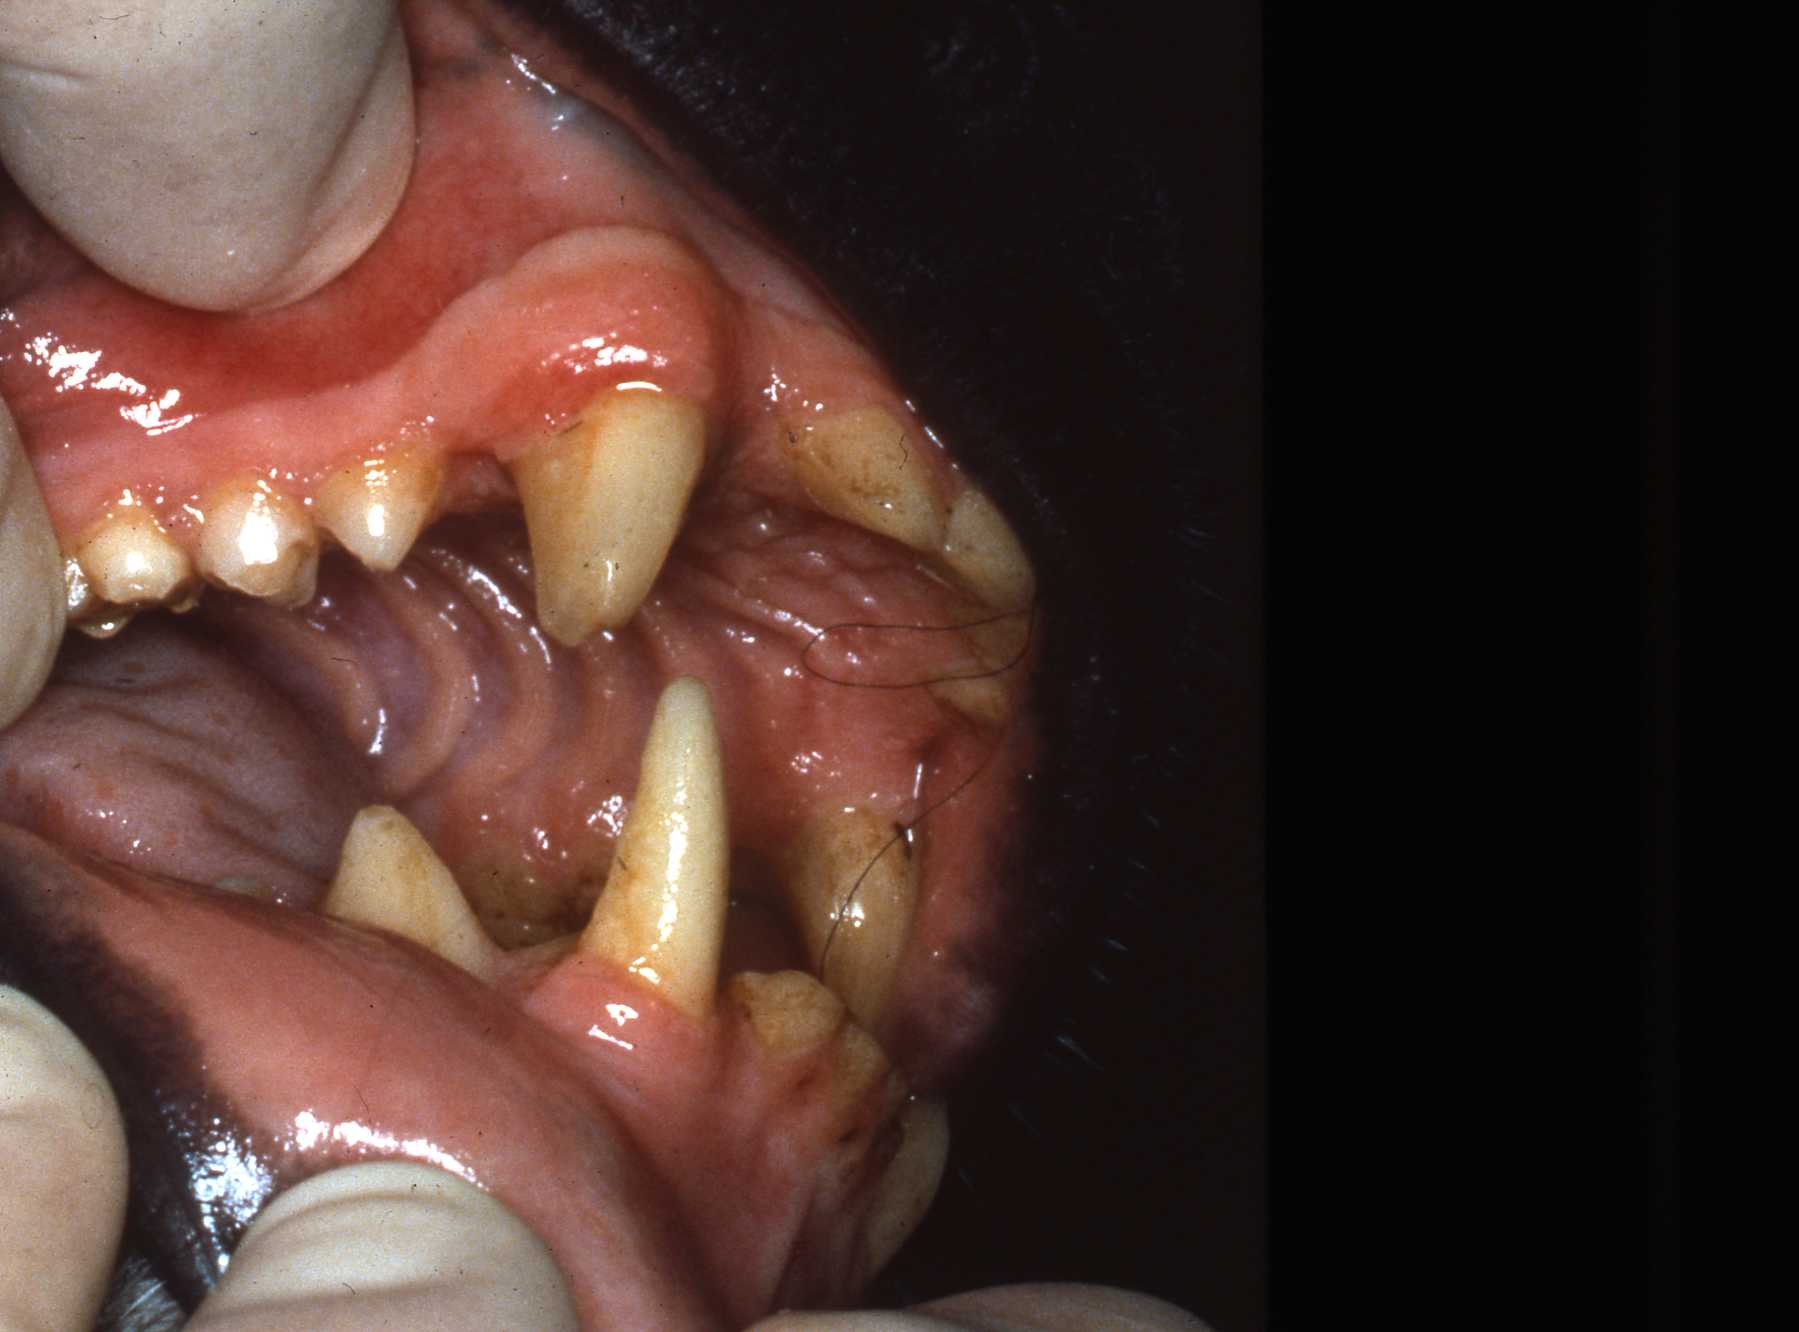

Periodontal Disease

The next most common pathosis encountered is periodontal disease. Again, improvement in diets has reduced this disease. I strongly believe that besides nutrients, diet texture is very important in optimizing oral health, minimizing periodontal disease. I believe that soft or pelleted foods that do not stimulate and challenge the dentition and periodontium may contribute to periodontal disease. Duplicating natural diets in this manner for diverse species is of course, not always possible, but zoos do make efforts to do so when they can.

In the gorillas and bonobos that were born and raised here at Milwaukee County Zoo, we have not had many periodontal problems. We have had adult gorillas come to us from other zoos with significant periodontal disease.

Most or our orangutans however, have had chronic, serious periodontal disease. All of our males have eventually lost all their teeth due to periodontal disease. That has not been the case with the females. We are not the only zoo that has had the chronic periodontal problems with orangutans. See Dr. Norm Stollers' paper: In the typical orangutan case that I have dealt with, there is not much accumulation of plaque or calculus. However, deep periodontal pocketing and bone loss progresses until the teeth become very mobile. I have not observed much bleeding in the most severe of these cases. We discussed preventive strategies and even tried chlorhexidine gluconate rinses to subdue the disease process. However, the orangs did not accept the products, probably due to the taste.

Exam: Fractured maxillary left canine (no. 15 or 207), extraoral chronic drainage tract adjacent to nostril and oral antral fistula where maxillary second molar had been extracted by veterinarian

Fractured canine with exposed pulp cavity